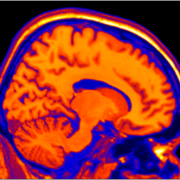

Welcome to the Deafness and Neural Plasticity Lab, run by Dr. Velia Cardin. We are interested in understanding how the human brain works, and what are the possibilities to enhance and change its function.

Our primary line of research is on human deafness. We want to understand how the brain reorganises in people who are deaf and hard of hearing, and how this impacts cognition and perception.